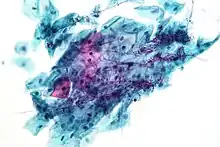

Candida

Candida species cause infections in individuals with deficient immune systems. Candida species tend to be the culprit of most fungal infections and can cause both systemic and superficial infection.[6] Th1-type cell-mediated immunity (CMI) is required for clearance of a fungal infection. Candida albicans is a kind of diploid yeast that commonly occurs among the human gut microflora. C. albicans is an opportunistic pathogen in humans. Abnormal over-growth of this fungus can occur, particularly in immunocompromised individuals.[7] C. albicans has a parasexual cycle that appears to be stimulated by environmental stress.[8]